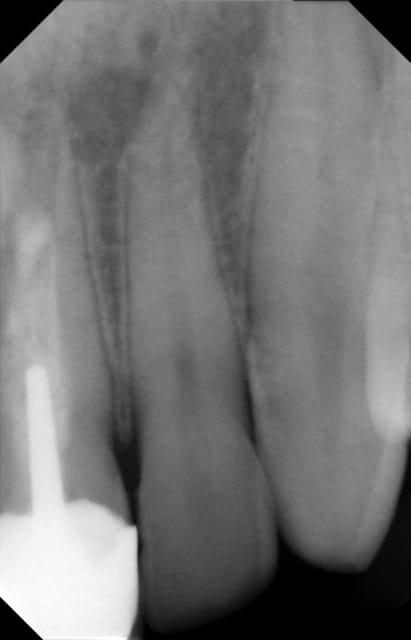

Monsieur R se présente en consultation avec pour motif douleur au niveau apical de 21 22. Adolescent il avait subi un trauma sur 21 qui avait été dévitalisée et couronnée.

Radio: lésion endo et canal très large, et mal obturé.

Mon problème est le suivant: le diamètre apical doit être de 100/10ème.

Ci joint les radios préop et après avec obturation hydroxyde et provisoire. Je n'ai pas joint la radio lime en place : la LW est 20mm

la radio finale est bizarre : on dirait une fusée de ciment à l'apex, voire un dépassement de gutta. Es-tu sûr de ne pas avoir projeté un morceau de l'ancienne obturation canalaire au-delà de l'apex ? Si c'est le cas, je conseille un curetage et une obturation a retro just'après ton obturation canalaire.

Très honnêtement je ne pense pas qu'il s'agisse de Gutta car je viens de regarder mes radios perop et avant l'obturation au CaOH2 je n'avais pas cette ligne blanche.

En plus quand j'ai désobturé la dent, il n'y avait pas de gutta mais uniquement des restes de ciment (ça craint pour le pauvre patient).

Mon CaOH2 est radio opaque (ultra calXS): en fait c'est allé au delà de l'apex. A la fac, mon prof m'a dit que quand ça arrivait ça n'était pas grave...

Voilà sinon je n'ai pas raconté la suite de mon cas : j'ai obturé avec l'aide de mon confrère à la biodentine et puis j'ai réalisé mon inlay core et ma coiffe pour l'étanchéité. Il y a une disparition des signes cliniques et la lésion radio semble commencer à se résorber. j'effectue des contrôles réguliers et j'ai bien averti le patient qu'en cas de récidive ou de résorption il faudra réaliser une obtu à rétro. En tout cas j'ai essayé au mieux de rétablir une étanchéité par voie antérograde!